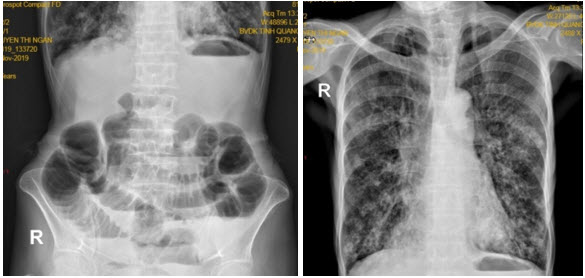

Bệnh nhân được chụp Xquang bụng: các quai ruột non giãn lớn kèm mức hơi dịch. Xquang phổi : hình ảnh dày thành kèm giãn phế quản dạng tổ ong (chụp nằm) (Hình 2). Siêu âm ổ bụng thấy hình ảnh giãn kèm tăng nhu động một số quai ruột non.

thoatvi2

Hình 2. Xquang bụng và ngực